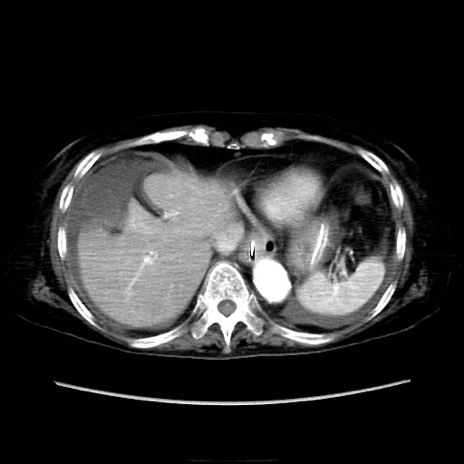

症例40(横断像)

【症例】90歳代女性

【主訴】腹痛・嘔吐

【現病歴】 食欲低下、嘔吐があり昨日他院受診。肺炎と診断され入院となる。入院後より腹部全体に圧痛あり。胃管留置され経過みていたが、症状持続するため、

当院転院となる。

【既往歴】胸椎圧迫骨折、胆石症

【身体所見】腹部:中央に激痛あり、圧痛あり、反跳痛不明

【データ】WBC 17100、CRP 18.82

他院CT

横断像